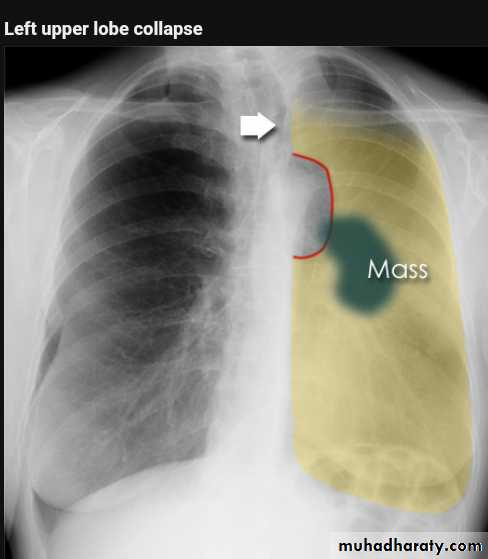

Left upper lobe collapse has distinctive features but can be challenging to identify on chest radiographs by the uninitiated.

Radiographic features

The left upper lobe collapses anteriorly becoming a thin sheet of tissue apposed to the anterior chest wall, and appears as a hazy or veiling opacity extending out from the hilum and fading out inferiorly . It thus reverses the normal slight increase in radiographic density seen as you move down the lung (due to increased thickness of the chest soft tissues).

Parts of the normal cardiomediastinal contour may also be obliterated where the left upper lobe, particularly the lingula abut the left heart border. The anterior parts of the aortic arch are also often obliterated from view.

In some cases the hyperexpanded superior segment of the left lower lobe insinuates itself between the left upper lobe and the superior mediastinum, sharply silhouetting the aortic arch and resulting in a lucency medially. This is known as the HYPERLINK "http://radiopaedia.org/articles/luftsichel-sign" luftsichel sign.

The left hilum is also drawn upwards, resulting in an almost horizontal course of the left main bronchus and vertical course of the left lower lobe bronchus.

Radiology of BGCA

The appearance depends on the location of the lesion.

1.The more central lesions may merely appear as a bulky hilum, representing the tumor and local nodal involvement the lesion is irregular in outline have spiky or sun ray spiculation .

2.Lobar collapse may be seen due to obstruction of a bronchus. When the right upper lobe is collapsed and a hilar mass is present, this is known as the Golden S sign.

3.A more peripheral location may appear as a rounded or spiculated mass. Cavitation may be seen as an air-fluid level , more to be large cell CA .